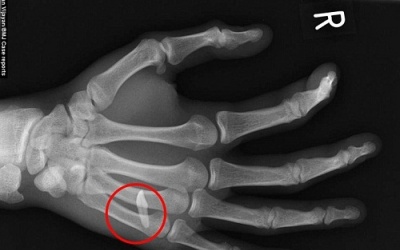

06/05/2015 17:35

Các bác sỹ vô cùng ngạc nhiên khi phát hiện chiếc răng cửa nhọn hoắt cắm sâu giữa các ngón tay của nam thanh niên.